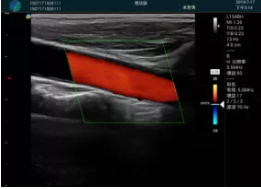

頸動脈血流充盈飽滿,無外溢

肝內(nèi)血管顯示清晰,血流敏感無外溢